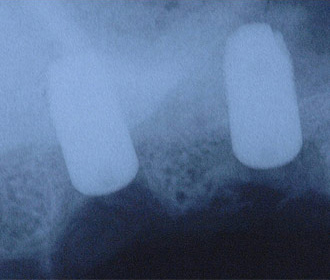

インプラント治療直後のレントゲン写真。

網目状のものがチタンメッシュ、ピンで骨に固定。 -